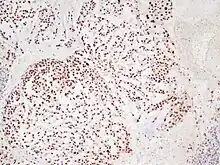

In 2015 the first consensus guidelines for the diagnosis and treatment of chordoma were published in The Lancet Oncology.[13] These tumors express brachyury and cytokeratin, which can be detected by immunohistochemistry.

There are three histological variants of chordoma: conventional,[14] chondroid and dedifferentiated.

- The histological appearance of classical chordoma is of a lobulated tumor composed of groups of cells separated by fibrous septa. The cells have small round nuclei and abundant vacuolated cytoplasm, sometimes described as "physaliferous" because of their cytoplasmic vacuoles, and their resemblance to the physalis plant.